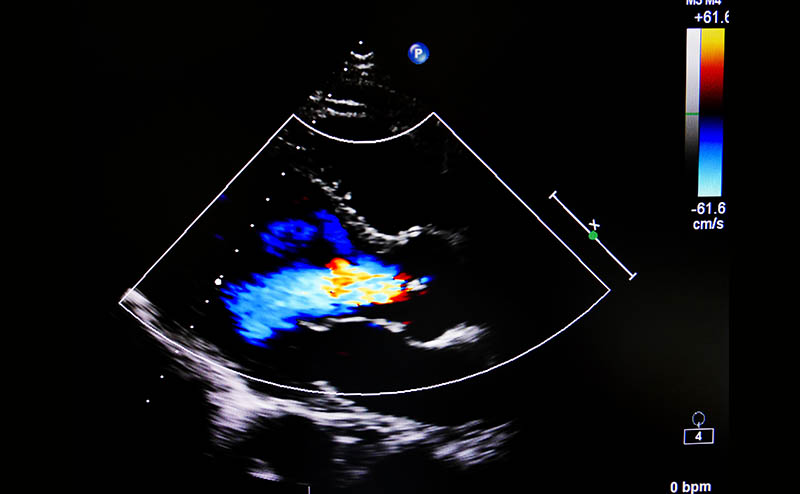

Figure 1. Severe regurgitant lesions associated with severe, acute MR

Color Flow Doppler (CFD) evaluation can then be performed, and is the most essential component of the valvular assessment. CFD can not only diagnose MR by discovering the presence of a regurgitant jet, but also help in determining its mechanism, severity, and hemodynamic impact. Once a regurgitant jet is identified, evaluate the jet’s three main components and direction of flow. Jet direction consists of three categories: central, eccentric, and multiple jets. In the presence of a flail leaflet, the regurgitant jet is typically located opposite to the affected leaflet (anterior flail leaflet = posterolateral jet, posterior flail leaflet = anteromedial jet). Presence of an eccentric jet should be considered severe until proven otherwise, and should alert you to the possibility of structural abnormalities.2 Multiple jets in unpredictable directions are often seen in patients with endocarditis.

The patient continued to demonstrate symptoms and vitals consistent with shock. Given concern for fluid overload without clear etiology, further investigation was done with point-of-care cardiac ultrasound by a more experienced practitioner while awaiting comprehensive echocardiography. This showed left atrial dilation but again normal LV size and function. Color flow doppler was applied, showing a posterolateral eccentric MR jet. On acquisition of higher quality images, a flail leaflet could be visualized. Review of further records showed a TTE from ~2 years ago quantifying the patient’s mitral regurgitation as mild. Consultation with cardiology at the time had revealed mitral annular calcification as the suspected etiology.